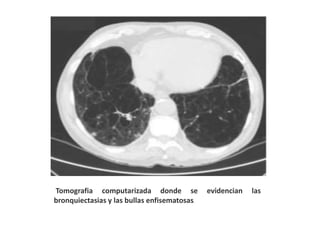

Tomografia computarizada donde se evidencian las

bronquiectasias y las bullas enfisematosas.

Tomografia computarizada dondese evidencian las bronquiectasias y las bullas enfisematosas.